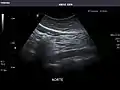

Aorta

Aorta: Visualized portions normal in caliber, 16 x 15 mm.